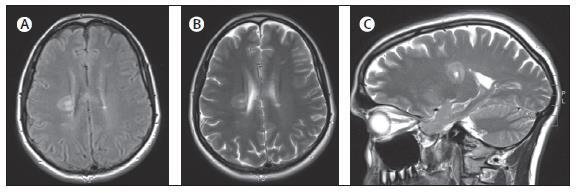

3. MRI 显示在右侧脑室旁白质的同心圆硬化病灶。A 图为 Flair 像,B 图为轴位 T2 像,C 图为矢状位 T2像,该例女性患者 36 岁,主因晨起出现突发左侧偏瘫就诊,起初被认为是卒中。注意在两侧大脑半球深部均出现伴随的更典型的脱髓鞘病变。

Balo 病变和多发性硬化之间的关系还不清楚。Balo 同心圆硬化可能是多发性硬化的一个变异型或一个单独的但又相关性的疾病。显然,传统的多发性硬化和 Balo 病变不仅仅只是病理学表现方面的重合。Balo 病变可以发生在除复发缓解型之外传统的多发性硬化发生的临床过程中。至少有 55% 存在 Balo 或 Balo 样病变的患者表现为 MRI 显示的典型多发性硬化病变 ( 图 2)